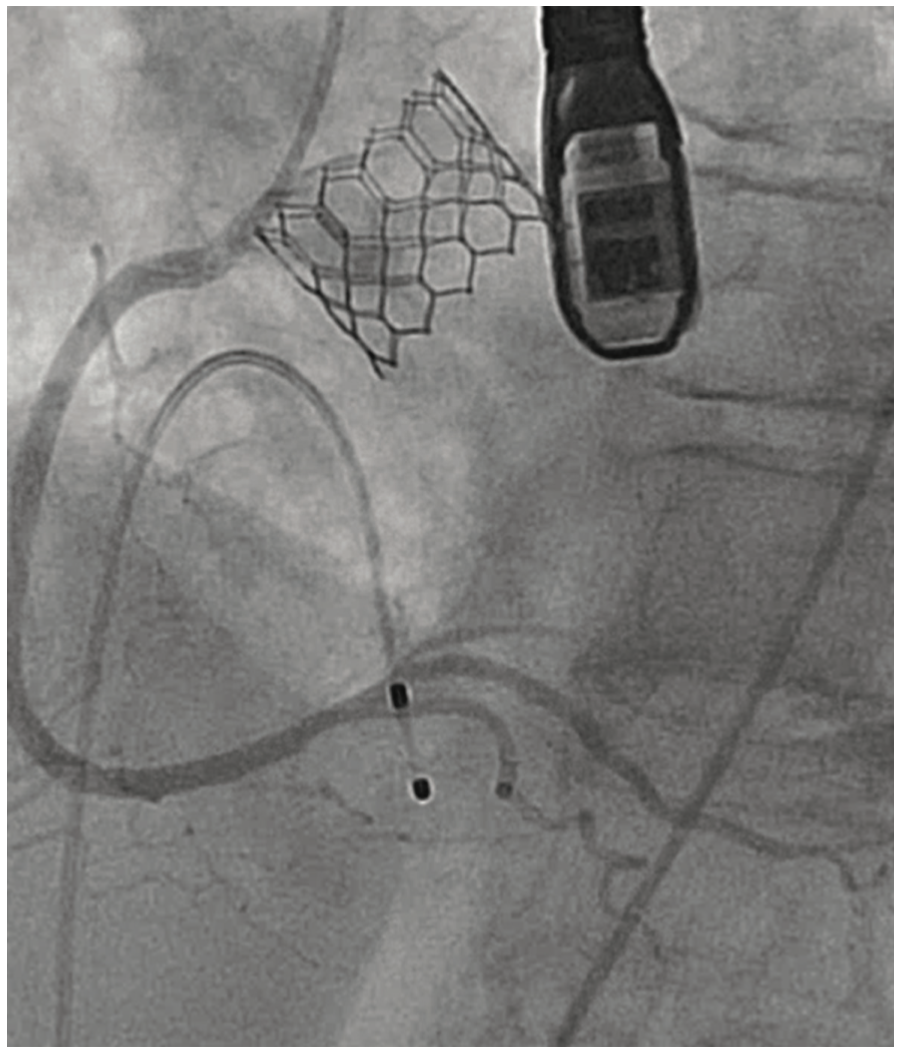

An 81-year-old female with symptomatic severe aortic stenosis, logistic EuroSCORE I (European System for Cardiac Operative Risk Evaluation) of 14.46%, EuroSCORE II of 3.44%, and Society of Thoracic Surgeons (STS) estimated surgical mortality of 3.371%, underwent TAVR. Transthoracic echocardiogram (TTE) showed a heavily calcified aortic valve with a mean gradient of 68 mmHg, aortic valve maximum velocity (Vmax) of 4.2 m/sec, calculated aortic valve area of 0.8 cm2, and normal left ventricular systolic function. Computed tomography angiography (CTA) demonstrated heavily calcified aortic root, leaflets, and annulus. Transfemoral implantation of a 23 mm Sapien 3 (Edwards Lifesciences) valve was performed (Figures 1-2). Using a 20 mm balloon for pre-dilation, the valve was implanted successfully in a 50-50 position (Figure 3). The immediate post-deployment aortogram showed leakage of dye outside the left sinus with no evidence of cardiac tamponade. Despite that fact, the patient developed immediate hemodynamic collapse. QRS widening and ST-elevation were visible on the monitor. Narrowing of the left main coronary artery (LMCA) with reduced TIMI flow (0-1) was evident in angiographic images (Figures 4-5). The patient had a cardiac arrest, cardiopulmonary resuscitation was initiated, and she went into cardiogenic shock. The patient stabilized with the placement of venoarterial extracorporeal membrane oxygenation (VA-ECMO) and the insertion of the Impella device (Abiomed) (Figure 6). An emergent percutaneous intervention was performed within minutes from collapse by the deployment of two drug-eluting stents from the LMCA into the left anterior descending (LAD) coronary artery (Figure 7) using the Culotte technique with final kissing-balloon dilatation. After the restoration of coronary flow, the patient was admitted to the cardiothoracic intensive care unit. She remained stable. The ECMO and Impella implant was removed after 7 days. Postprocedure on day 14, the patient was discharged to a rehabilitation facility. Echocardiography showed a well-functioning valve with acceptable residual gradient and mild to moderate paravalvular leak.